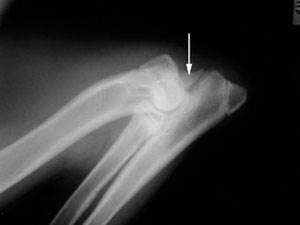

Клинический осмотр может определить, является ли локтевой сустав отечным или болезненным, несмотря на то, что первоначально хромоту может быть трудно локализовать. Подтверждение диагноза дисплазии локтевого сустава производится путем выполнения дальнейших исследований (КТ или рентгенографии).

С помощью рентгена можно определить, есть ли собаки дисплазия локтевого сустава. Делается это путем идентификации основной проблемы или остеоартрита, появляющегося в результате. Три кости (плечевая кость, лучевая и локтевая кость) объединяются для формирования локтевого сустава, и они накладываются на рентгенограммах. Это делает идентификацию основного поражения проблематичной в некоторых случаях.

Компьютерная томография является превосходным методом изучения структуры сустава и определения точного характера дисплазии локтевого сустава. Это дает дополнительную информацию в дополнение к рентгенографии и это может быть полезно при планировании хирургического лечения, особенно в более сложных случаях.